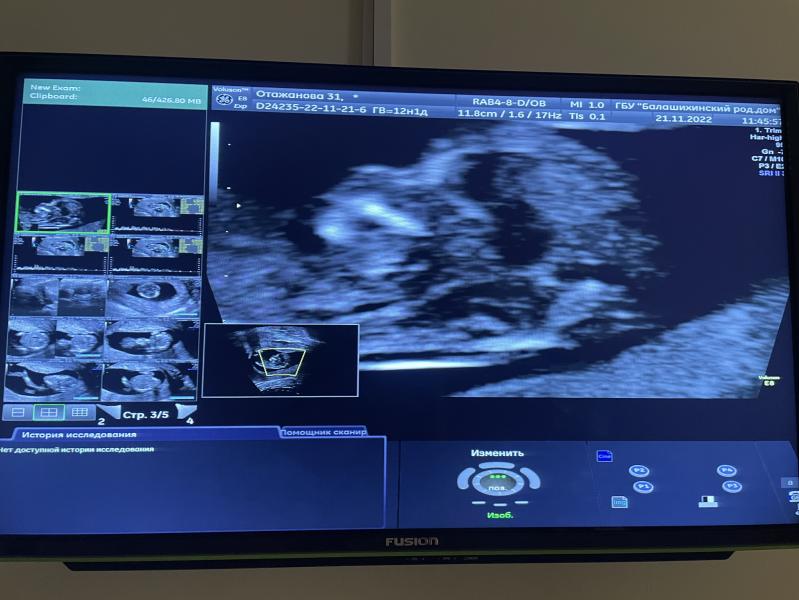

Девочки, милые, я сегодня прошла первый скрининг😭*слезы счастья*

Все у малыша в норме по узи, пол пока загадка, но я и не тороплюсь😌

Узистка, вручая мне фото, сказала, что нужно хранить в памяти этот прекрасный носик😊

Теперь жду результаты по крови